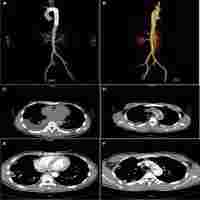

| Abstract | Background Aortoesophageal fistula (AEF) is a rare condition characterized by communication between the aorta and esophagus. AEF caused by an esophageal foreign body is even rare, and there is currently no recommended standard treatment protocol. We report a case of delayed aortic rupture after the endoscopic removal of a fish bone, which was successfully treated with a combined approach of vascular stenting and thoracic surgery. Case presentation A 33-year-old man presented to the hospital after experiencing chest discomfort for 3 days following the accidental ingestion of a fish bone. Under endoscopic guidance, the fish bone was successfully removed, and the patient was subsequently admitted for medical therapy. On the fourth postoperative day, the patient suddenly developed hematemesis, and chest computed tomography angiography revealed the presence of an AEF. This necessitated urgent intervention; hence, thoracic surgery was performed and a vascular-covered stent was placed. Following the surgical procedure, the patient received active medical treatment, recovered well, and was successfully discharged from the hospital. Conclusions In patients with esophageal perforation caused by foreign bodies, hospitalization for observation, computed tomography angiography examination, early use of antibiotics, and careful assessment of aortic damage are advised. Thoracic endovascular aortic repair and esophageal rupture repair may have benefits for the treatment of AEF. |